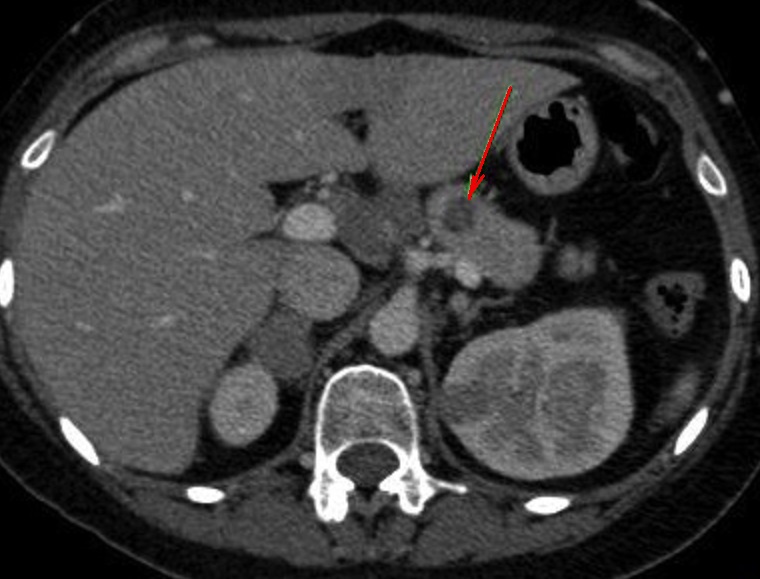

Image

coupe axiale . |

|

Aspect lesionel TDM une masse a hypodense

, homogene mal limitee situe du corps pancreas(

fleche rouge . Rehaussement legere du tumeur apres

injection de contrast intraveineuse . Image

radiologique TDM plus contrast intraveineuse , coupe

axiale . |